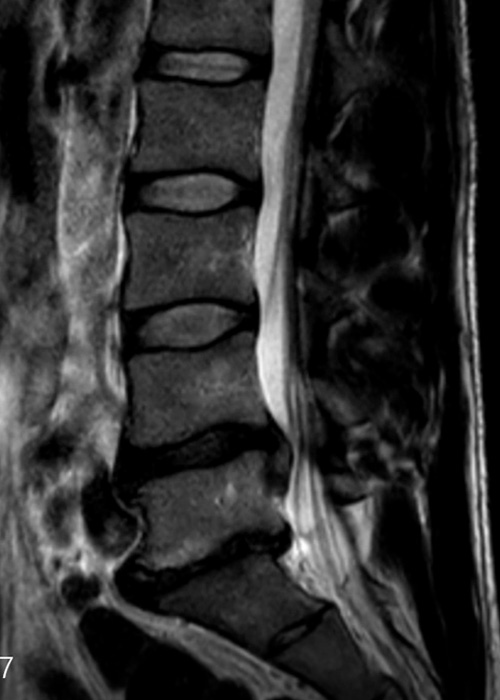

Tras realizar las pruebas de diagnóstico pertinentes y proceder a una exhaustiva exploración, se le diagnostica una hernia discal de gran tamaño entre la 4ª y la 5ª vértebra lumbar, que ocupa prácticamente todo el canal y comprime las raíces y tejido neurológico que se alojan en la columna.

Tras barajar todas las opciones posibles se le propone una Endoscopia Avanzada de Columna para extraer la hernia de forma ultramínimamente invasiva